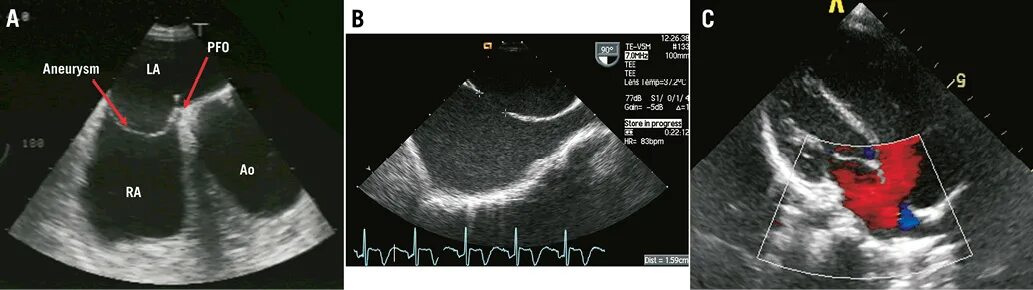

Мпп у новорожденного